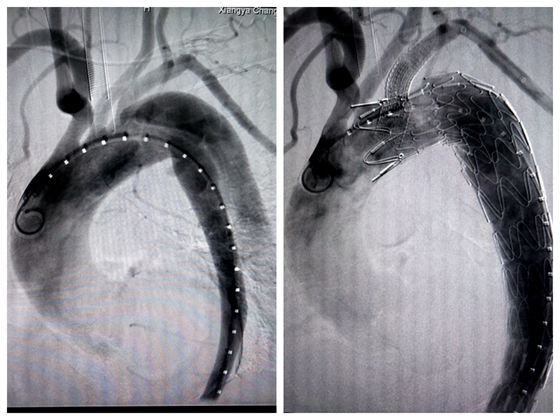

手术在介入手术室进行,由放射介入科和心胸外科联合,介入科主任胡康新及心胸外科主任黄日茂教授教亲自上台指导,在DSA引导下,全麻穿刺股动脉,并在左上臂中段行肱动脉切开,先经股动脉插入带黄金标记的6F猪尾巴导管,左前斜位投照下,行主动脉造影,详细了解主动脉夹层的部位、形态、大小、范围及破口距左锁骨下动脉开口的距离,然后经股动脉送入导引导丝,确认导丝在主动脉真腔后,植入预先在体外开窗的大动脉覆膜支架。最后,经左肱动脉植入一个覆膜血管支架于左锁骨下动脉主动脉覆膜支架开窗处,以保证左锁骨下动脉开口不受大动脉覆膜支架的覆盖,进而保证左锁骨下动脉及左锥动脉动的正常供血。

手术前后对比图